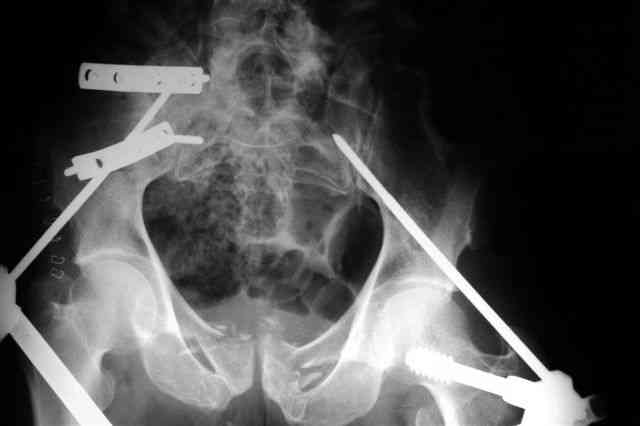

Я помню технику транссакральной фиксации тазового кольца длинными 5 мм Шанцами - повреждения типа В, в этом же случае задний отдел тоже вовлечен

т.е комбинированная нестабильность, поэтому вопрос - достаточно ли только двух Шанцев для стабилизации таза? Что вы думаете об anterior Right SI joint plating + tension band plating from the back.?

PS после фиксации бедра под Эопом посмотрел инлет и аутлет проекции, насколько репонируемо смещение правой половины таза *невооруженными*

руками - никаких шансов улучшить позицию иначе бы конечно воспользовался длинными Шанцами сразу после бедра.

Элегантная фиксация, поздравляю.Но ваш случай : одноплоскостная горизонтальная нестабильность Tyle B2.2 отличен от представленного мной - у

моего больного + вертикальная нестабильность за счет повреждения правого крестцово-подвздошного сочленения и перелома заднего отдела подвздошной

кости- С2 тип. Поэтому и возникла дилемма : выбор оптимальной фиксации заднего отдела:

По-поводу фиксации таза спонгиозными винтами. Данный способ все-таки показан для фиксации повреждения крестцово-подвздошного сочленения или переломов крестца. Мне кажется, что в данной случае ситуация иная - имеется перелом "основания" крыла подвздошной кости (в который вовлечена и поверхность, составляющая крестцово-подвздошное сочленение). Не уверен, что фиксация данного повреждения (и заднего полукольца) винтами будет стабильной, так как именно на уровне 1-2 крестцовых позвонков (где обычно вводят винты) линия перелома уходит в латеральном направлении от крестцово-подвздошного сочленения.

По-поводу репозиции костей таза. Производить репозицию костей все-таки необходимо. Пока я не встретил информации, сколько времени прошло с момента травмы, но одномоментно низвести правую половину таза может быть тяжело, учитывая и наличие перелома бедренной кости (что затруднит тракцию за нижние конечности).

Я просмотрел томограммы и у меня создалось впечатление, что винтам есть за что *зацепиться*. В сочетании с 5 мм Шанц винтами, проведенными через нижне-переднюю ость спереди назад через КП сочленения -стабильность тазового кольца должна восстановиться. - Это , конечно, при условии , что закрытая рнепозиция будет успешной.

PI>По-поводу репозиции костей таза. Производить репозицию костей все-таки необходимо. Пока я не встретил информации, сколько времени прошло с момента травмы, но одномоментно низвести правую половину таза может быть тяжело, учитывая и наличие перелома бедренной кости (что затруднит тракцию за нижние конечности).

Травма произошла 22 или 23 декабря, ко мне больной попал 26 декабря, 3 января -остеосинтез перелома бедра и внутр.лодыжки.